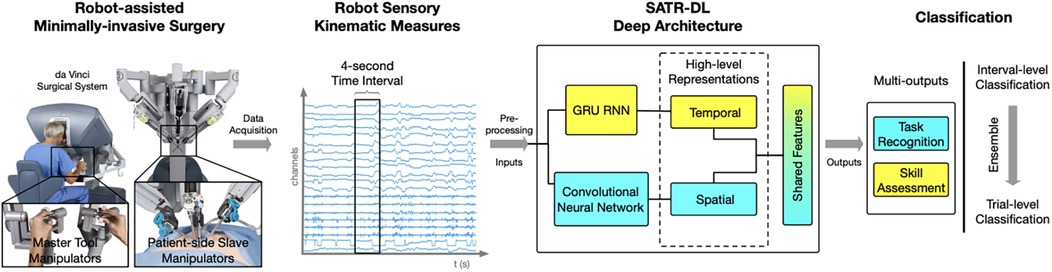

4.2.10 da Vinci Surgical System

Hand motion has also been tracked using advanced systems like the da Vinci Surgical System. Wang and Fey used an end-to-end motion analysis framework with a multioutput deep learning architecture (SATR-DL) to track surgical trainee motions as raw kinematics during specific tasks (30). This method allowed for the representation of both spatial and temporal dynamics of hand motion during surgical tasks. Once the raw motion kinematics had been recorded, they could be input into SATR-DL to recognize the specific task and assess skill level (Figure 10) (30).

Figure 10. Surgical skill assessment and task recognition. Wang and Fey (30) presented an analytic framework with a parallel deep learning architecture, SATR-DL, to evaluate trainee performance and to recognize surgical training activity in robotic-assisted surgery. They aimed to improve surgical skill assessment and task recognition with deep neural networks. This figure illustrates a complete framework stated in this study, flowing from left to right. The far left image shows the da Vinci Surgical System, with which a 4-second clip of the surgical motion is captured using da Vinci end effectors. These data are then captured and converted to kinematic measurements, which are then analyzed by the SATR-DL deep architecture. Once analyzed, the measurements are classified into task recognition and skill assessment. GRU, gated recurrent unit; RNN, recurrent neural network; SATR-DL, skill assessment and task recognition with deep learning. Used with permission from Wang Z, Fey AM. SATR-DL: Improving Surgical Skill Assessment And Task Recognition In Robot-Assisted Surgery With Deep Neural Networks, 2018 40th Annual International Conference of the IEEE Engineering in Medicine and Biology Society (EMBC). 2018;1793–1796.

4.3.2 Objective skill assessment and task recognition in surgery

Objective skill assessment and task recognition in surgery have also been areas of interest in using deep neural networks. Wang and Fey created an analytic framework with a parallel deep learning architecture, SATR-DL, to assess trainee expertise and recognize surgical training activity (30). According to the results, the deep learning model was able to successfully recognize trainee skills and surgical tasks, including suturing, needle passing, and knot tying. The reported accuracies of the deep learning model were 0.960 and 1.000 in skill assessment and task recognition, respectively. Ultimately, the findings underscored the potential of these neural networks for efficient quantitative assessments in surgical applications, including robotic surgery (30).